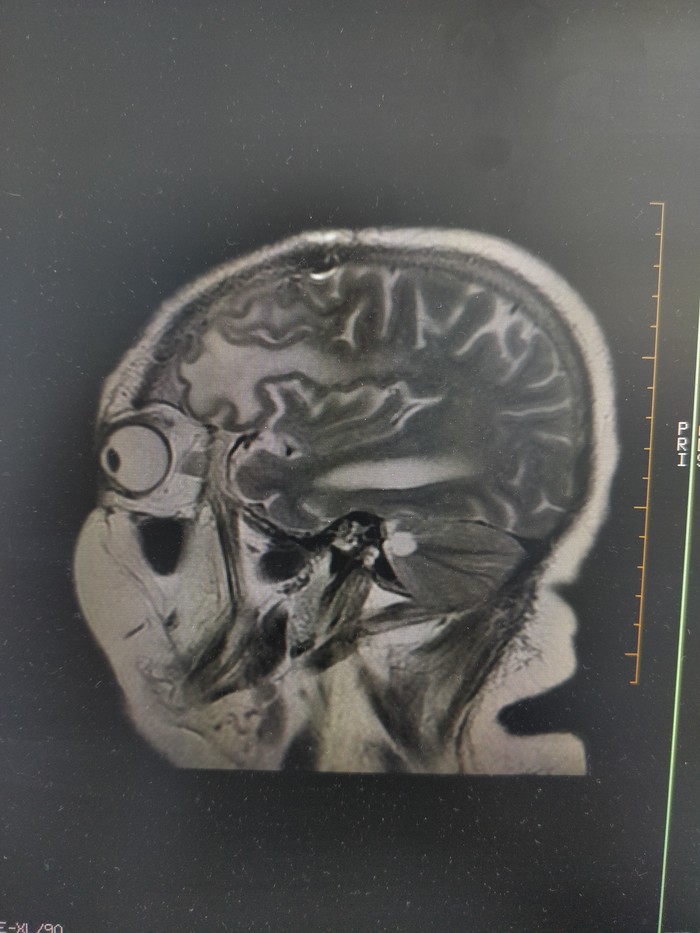

3. Колени в этой проекции всегда страусы.